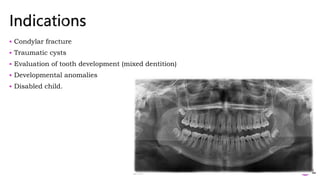

 Condylar fracture

 Traumatic cysts

 Evaluation of tooth development (mixed dentition)

 Developmental anomalies

 Disabled child.